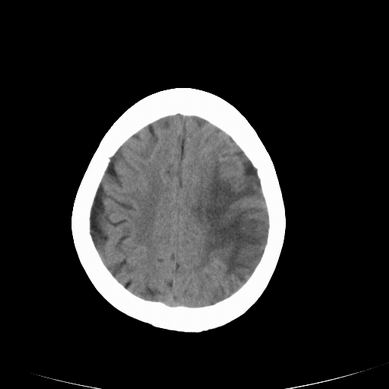

以下是引用jsgdoctor在2008-7-16 23:11:00的发言:[br]左侧大脑中动脉供血区脑梗塞